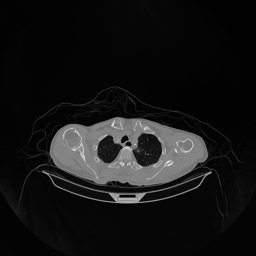

The results for simulated noisy data are shown in Fig. 2. The first and third rows display two representative slices from the test set, and the second and fourth rows present the corresponding error maps. The traditional WCE method suppresses cupping artifacts and recovers some missing anatomical structures but still shows noticeable deviations from the ground truth. Predictions from the four diffusion-based models demonstrate a markedly improved ability to restore anatomical structures. Among them, cDDPM fails to fully reconstruct the patient bed and retains residual noise in its outputs. This noise is attributable to an incomplete reverse denoising process rather than residual Poisson noise, as evidenced in our noise-free experiments (Fig. 5 in the Appendix). PatchDiffusion, diffusionGAN, and I2SB achieve similar visual quality, with I2SB producing the cleanest and most consistent reconstructions.

Quantitative results in Tab. V further confirm I2SB’s superiority over conventional deep learning methods such as FBPConvNet and Pix2pixGAN across RMSE, PSNR, and SSIM. Compared to other diffusion models—including cDDPM, PatchDiffusion, and cLDM—I2SB delivers higher image quality, while diffusionGAN achieves comparable quantitative performance. However, I2SB demonstrates a significant advantage in inference efficiency, as summarized in Tab. IV.